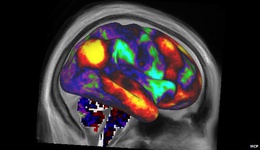

ایسنا: پژوهشگران دریافتهاند که تفاوت افراد در جهتگیریهای سیاسی با تفاوتهای موجود در ساختار مغز آنها در ارتباط است.

به گفته محققان دانشگاه لندن افرادی که خود را لیبرال مینامند از قشر قدامی کمربندی بزرگتر و طرفداران حزب محافظهکار از بادامه مغزی بزرگتری برخوردارند.

به گفته محققان لندن، بر اساس اطلاعات موجود در مورد عملکرد این بخشهای مغز، تفاوتهای ساختاری با گزارشهای روانشناسی موجود در مورد توانایی بیشتر افراد لیبرال در کنار آمدن با موقعیتهای متناقض و همچنین قابلیت بالای محافظهکاران در شناسایی خطر، سازگار است.

دانشمندان پیش از این برخی از صفات روحی افراد را به عنوان پیشبینی کننده جهتگیری سیاسی آنها شناسایی کرده بودند و اکنون این دانشمندان به پیوند این صفات شخصیتی با ساختار خاص مغزی پرداختهاند.